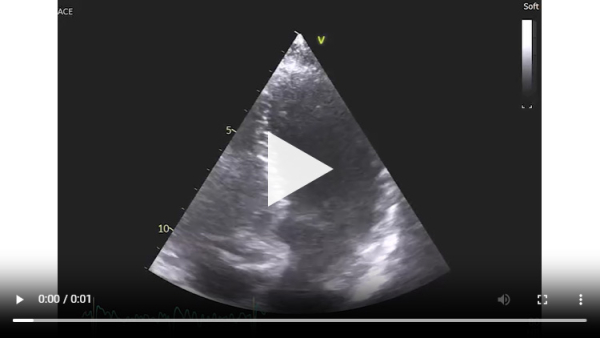

Vidéo 1 : échocardiographie 2D en incidence parasternale grand axe

En effet, c’était le diagnostic à éliminer en priorité devant les symptômes présentés par la patiente avec un ECG légèrement microvolté et des éléments évocateurs d’une amylose cardiaque à l’échocardiographie : hypertrophie VG très minime mais > 10 mm chez une femme (> 11 mm chez un homme) (cf Vidéo 1 et Image 1), hypertrophie VD à 6 mm (>5 mm) (cf Image 9) et l’altération des strains longitudinaux basaux à l’AFI après valeurs préservées à l’apex (cf Image 7).